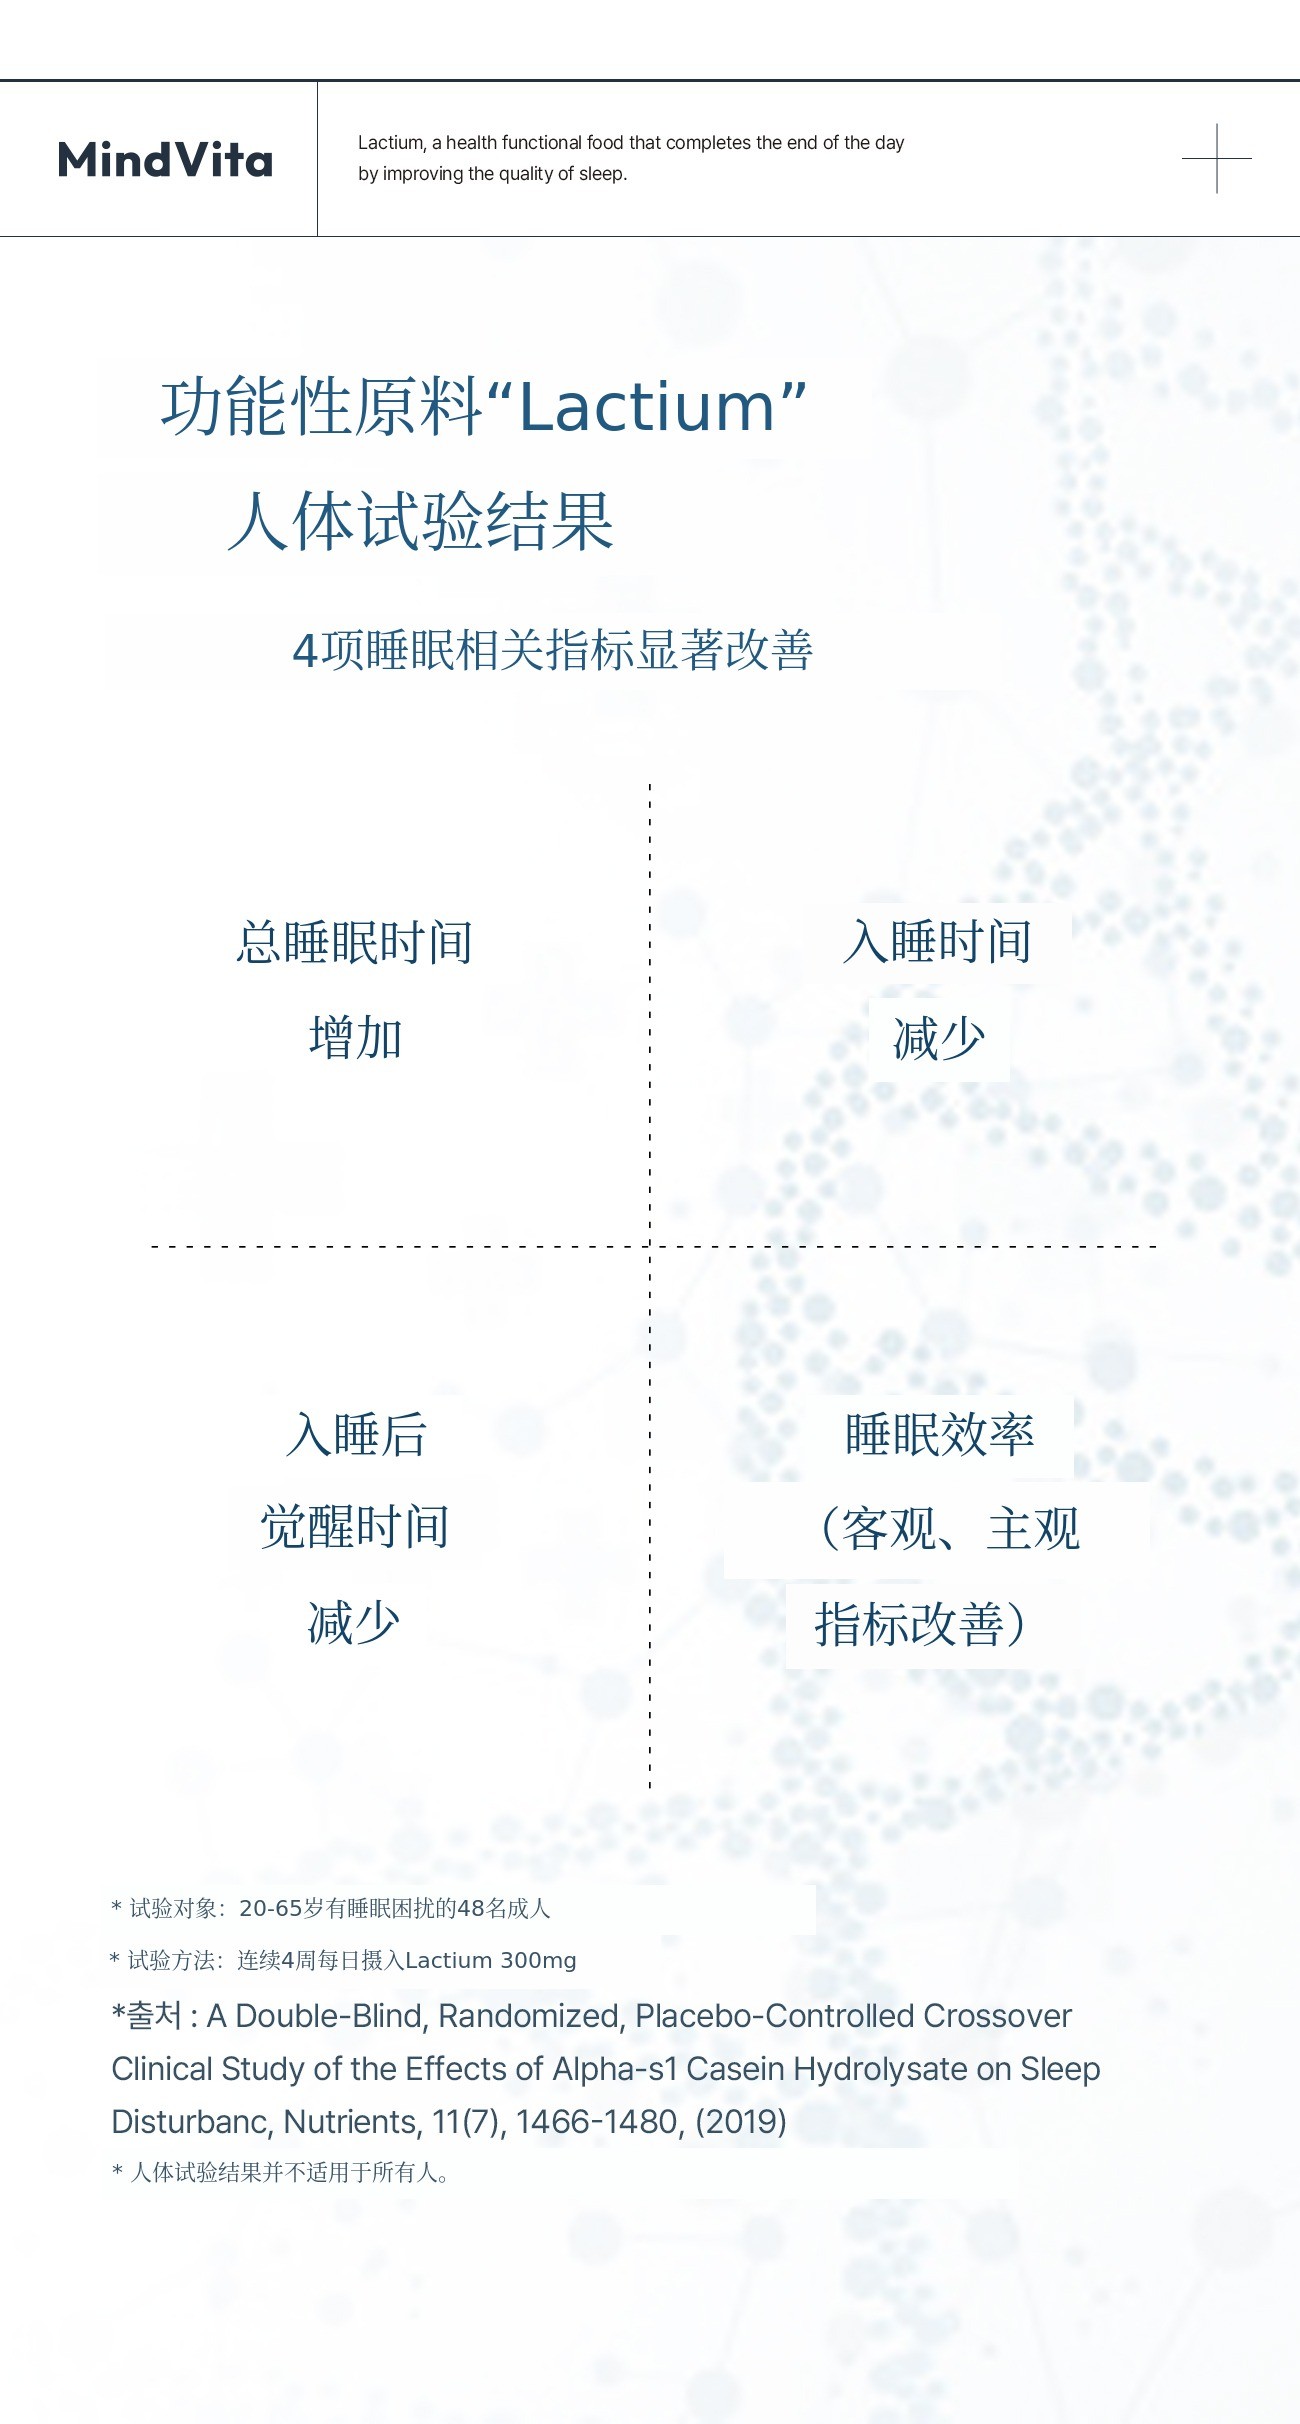

主要成分Lactium 是通过酶分解牛奶蛋白获得的乳蛋白水解物,属于天然成分,能够抑制压力激素皮质醇的过度分泌,缓解紧张和焦虑,带来心理安定感。同时通过与大脑GABA受体的间接作用,温和降低妨碍睡眠的觉醒状态,无嗜睡或依赖性,自然引导入睡是其特点。